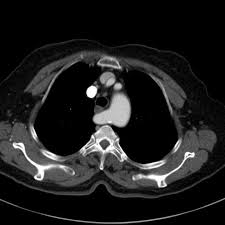

A peritoneal csf pseudocyst is a rare complication of ventriculoperitoneal shunt catheter placement. To counter a siphoning effect associated with upright posture many shunt systems also include an antisiphon device. Ventriculoperitoneal vp shunts are a device used to shunt cerebrospinal fluid in the treatment of hydrocephalus.

The external portion of the catheter is connected to a valve that regulates the flow of csf based on a preset pressure. Topics reviewed include the components and imaging appearances of the most common types of shunts and the utility of different imaging modalities for the evaluation of shunt failure. Historically shunt valves permitted a fixed amount of csf drainage.

Axr above shows the tip of the vp shunt has migrated into the right scrotum. Note redundancy of intraperitoneal catheter to allow for vertical growth of child black arrow c. As the name suggests a catheter is placed with its tip in the ventricle.